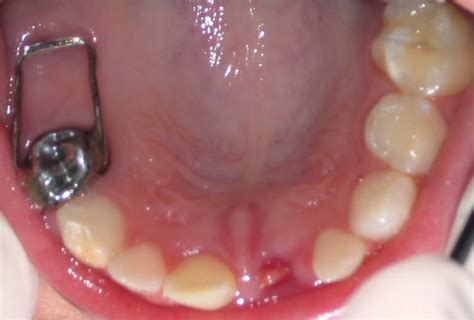

Ejemplo de Mantenedor de Espacio Banda-Lazo

Es crucial anticipar el proceso de anestesia y extracción al paciente, explicándole cada paso de manera clara y sencilla. La comunicación efectiva es clave para reducir la ansiedad y asegurar la cooperación del niño.